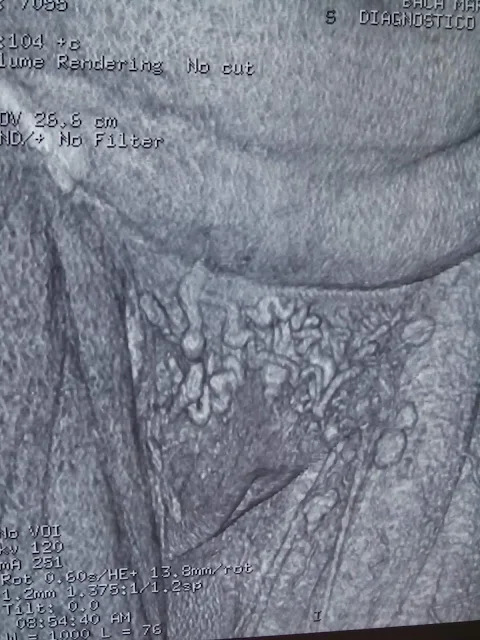

PACIENTE FEMENINA DE 48 AÑOS DE EDAD, CON ANTECEDENTE DE HISTERÉCTOMIA CON HEMORRAGIA IMPORTANTE HACE 10 AÑOS , POSTERIORMENTE DESARROLLA CON LOS AÑOS EDEMA DE MIEMBRO PÉLVICO IZQUIERDO, LA PACIENTE SE DIAGNOSTICA CON TROMBOSIS VENOSA PROFUNDA LLEVANDO MANEJO IRREGULAR CON ANTICOAGULACIÓN ORAL, DESDE HACE 2 AÑOS CON PRESENCIA DE LINFEDEMA Y CRECIMIENTO DE LA EXTREMIDAD PÉLVICA IZQUIERDA, LA PACIENTE SE SOMETE A REALIZACIÓN DE ANGIOTOMOGRAFIA CON LOS HALLAZGOS DE IMPORTANTE CIRCULACIÓN COLATERAL PÉLVICA POR TROMBOSIS DE VENA ILIACA IZQUIERDA, PACIENTE SE SOMETE ANTICOAGULACIÓN CON MEJORIA SIGNIFICATIVA DEL EDEMA Y POSTERIORMENTE CANDIDATA A COLOCACIÓN DE STENT VENOSO ILIACO.

CIRCULACIÓN COLATERAL PÉLVICA

TROMBO EN VENA ILIACA

LOS PADECIMIENTOS GINECOLÓGICOS COMPLICADOS ES MUY COMÚN LAS TROMBOSIS A NIVEL PÉLVICO, UN DIAGNÓSTICO OPORTUNO DISMINUIRÁ LAS SECUELAS A LARGO PLAZO EN ESTAS PACIENTES.